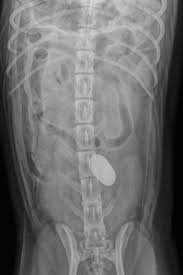

gi foreign body dog

• abdominal radiographs (X-rays)

Radiographs often help identify the presence and location of the obstruction.